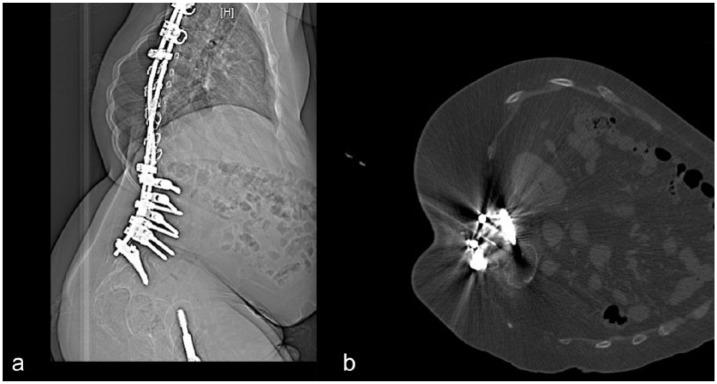

Cervical puncture to deliver nusinersen in patients with spinal muscular atrophy.

Neurology. 2018 Aug 14;91(7):e620-e624. doi: 10.1212/WNL.0000000000006006. Epub 2018 Jul 13.

Orthopedic Management of Scoliosis by Garches Brace and Spinal Fusion in SMA Type 2 Children.

J Neuromuscul Dis. 2015 Nov 21;2(4):453-462. doi: 10.3233/JND-150084.